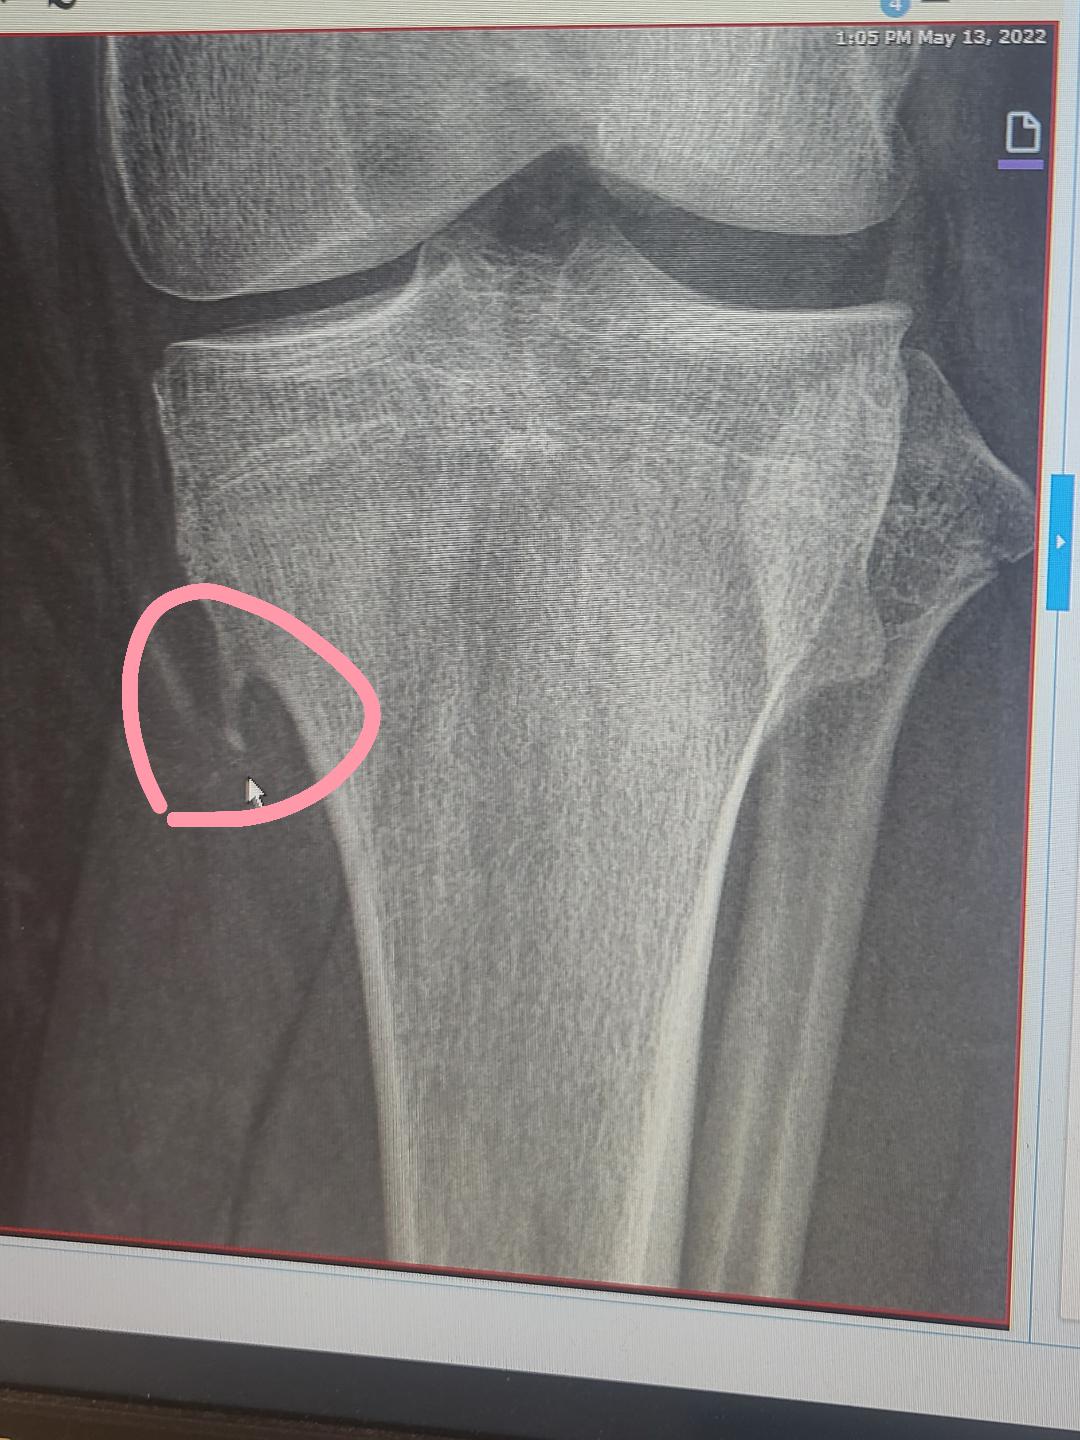

I have a defect that causes a piece of bone to grow out of my Genetic Knee Disorders Genetic biomarkers in osteoarthritis (oa) could serve as potential indicators for various disease parameters, including. Using crispr editing in mice and human cells, they pinpointed a genetic variant, present in billions of people, that affects the function of a key knee switch, changing knee shape. We sought to identify the genetic variants associated with knee pain in 171,516 subjects from. Genetic Knee Disorders.